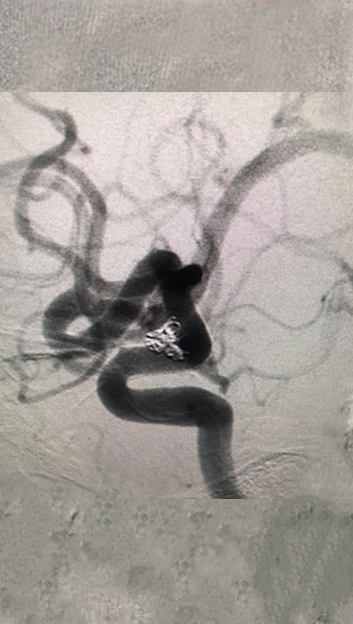

3.3)

填入5个超软圈,美敦力Prime系列对瘤壁压力非常低,对脆弱的血泡样动脉瘤安全有保障;弹簧圈圈体非常柔软,有利于致密栓塞,阻隔血流。

APB 3-8-3D、APB 2-4-3D 、APB 2-4-2D,APB 2-3-2D,APB 1-1-2D

4.1)

造影显示动脉瘤致密栓塞